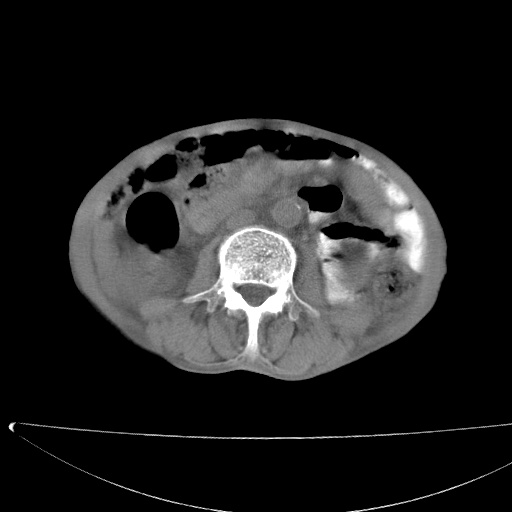

患者男70岁,上腹部不适1月。8年前有胃癌手术史。余病史不祥。

考虑胃癌复发并小网膜淋巴结转移侵及肝脏胆总管梗阻

考虑胃癌复发并腹腔内淋巴结转移。

1)胃癌术后,复发不排除。

2)肝脏转移瘤。

3)肝脏钙化灶。

4)胆囊增大。

5)腹膜后多发性淋巴结转移。

6)腹水。

建议:增强扫描。

考虑胃窦癌肝门转移

考虑胃癌复发并腹腔内淋巴结转移,胆总管受侵。

考虑胃窦癌肝门区淋巴结转移!

1)胃癌术后,不排除复发可能。2)考虑肝脏及腹膜后淋巴结转移瘤。3)肝内胆管扩张,胆囊增大。4)肝内胆管结石(或钙化)。5)脾脏钙化灶。6)腹水。7)右侧少量胸腔积液。

建议:行ct增强扫描检查。

1、胃癌根治胃空肠吻合术后,残胃癌?

2、肝门区占位性病变并胆道上段梗阻(肝内胆管扩张、胆囊增大),考虑肝门区淋巴结转移累及胆总管,建议ct增强扫描;

3、右侧胸腔少量积液、少量腹水;

4、肝右叶胆管结石。

肝门区占位性病变并肝内胆管扩张。

小网膜囊区及腹膜后肿大淋巴结。